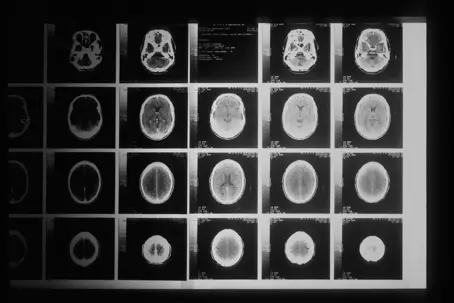

How does TBI affect daily life?

brain injury xray

A traumatic brain injury (TBI) can change everything about how you live. From memory issues to physical challenges, the effects often show up in everyday routines. Understanding how it impacts your life helps you plan and adjust.